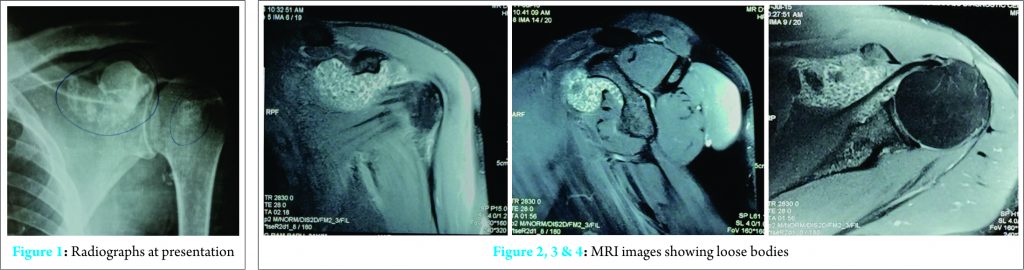

A 31-year-old man presented with pain and restricted movements of left shoulder since 6 months, which was insidious in onset and gradually progressive. He had no history of trauma,fever, loss of appetite or weight loss. No tenderness or warmth over shoulder joint was observed. There was restriction of movements in all directions. Routine pre-operative investigations (including liver function and renal function tests) were within the normal limit, serological investigation for rheumatoid arthritis was negative. X-ray of left shoulder showed multiple osseous loose bodies in subcorocoid region and shoulder joint overlapping on the bone [Fig. 1]. On MRI, multiple (2 to 3mm) rice bodies were visualized in the glenohumeral joint, subscapular recess and along the long head of biceps. There were large filling defects upto 8 – 12 mm in subscapular recess anterior to subscapularis muscle. Ac joint and rotator cuff appears to be normal [Fig 2, 3, 4].